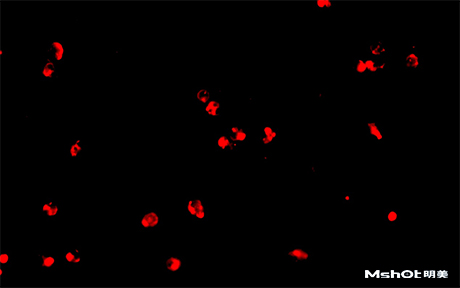

北京某試劑單位已有一臺(tái)奧林巴斯生物顯微鏡BX61,希望能進(jìn)行CTC檢測,在電腦中成像拍攝保存圖片,剛好我們在北京有辦事處,工程師了解到具體需求分析后提供一款明美數(shù)字?jǐn)z像頭MS23,搭配奧林巴斯BX61生物顯微鏡在40X觀察下,效果如圖::